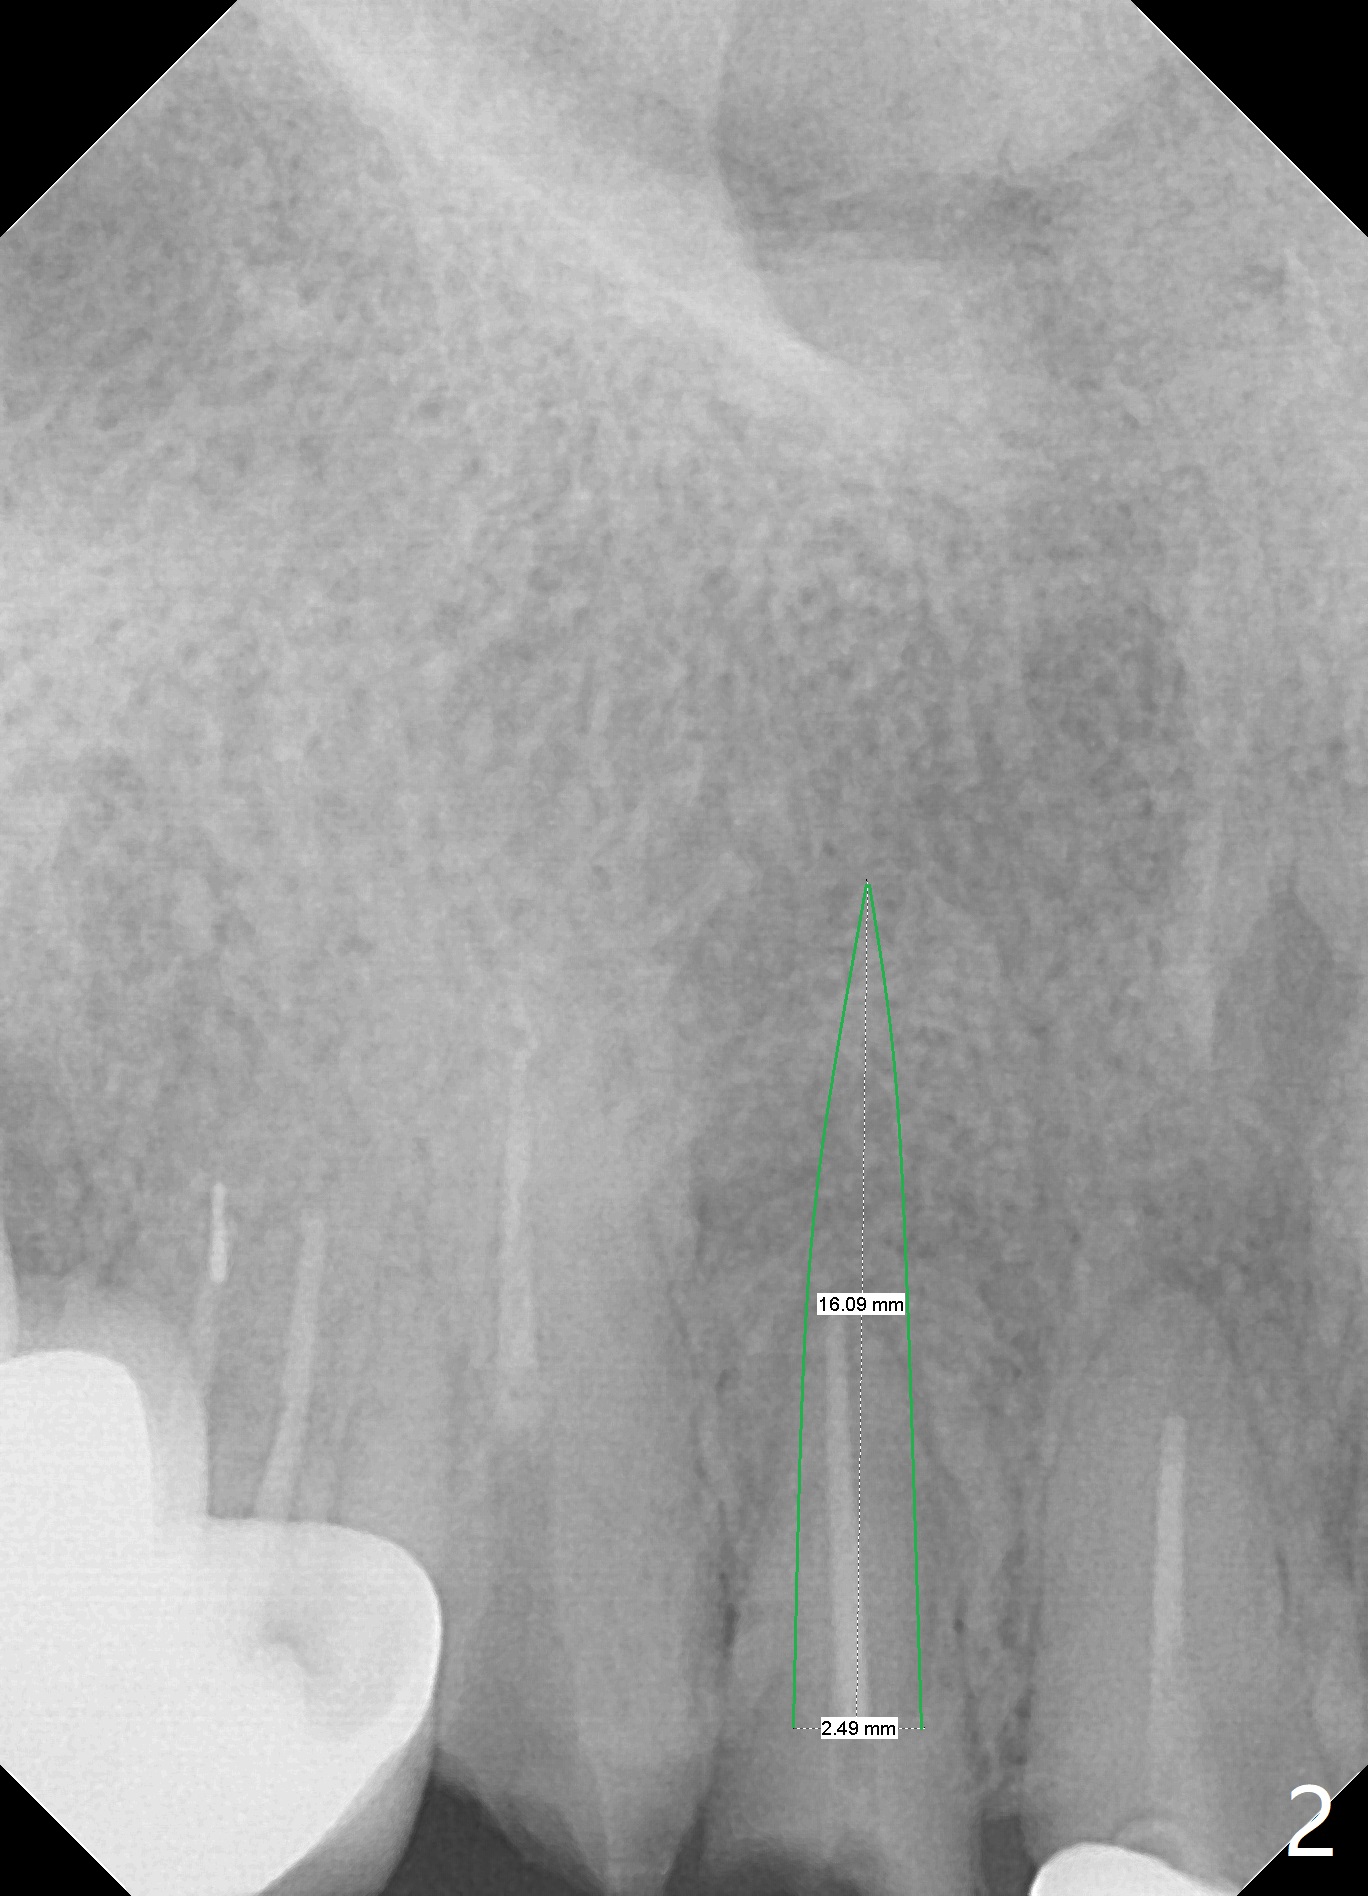

A 87-year-old woman requests implants following dislodgement of #6 and 7 crowns (Fig.1). In fact the crown at #6 is recemented. An implant will be placed at #7. To reduce the chance of buccal or palatal plate perforation, a 2.5x14 mm 1-piece implant will be used (Fig.2), in spite of a 4.5x20 mm tissue-level implant having been placed on the contralateral side (Fig.3). If the bone density at #7 turns out to be low, underprepare or use a larger implant. Prepare for socket shield.